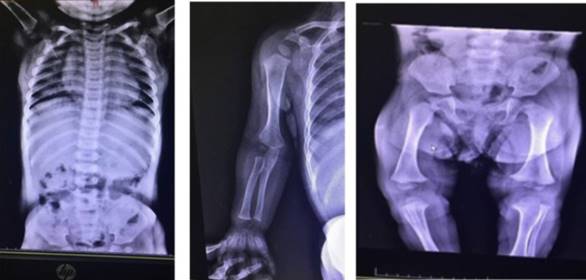

El crecimiento en peso, longitud y perímetro craneano según la edad se muestran en las (Figura 1), (Figura 2) y (Figura 3). En la (Figura 4) se muestra la evolución del peso de acuerdo a la longitud.

Figura 1: Gráfica del peso para la edad. Los puntos verdes indican los valores para esta paciente de acuerdo a la edad.

Para ello se realizaron radiografías que fueron analizadas por médicos imagenólogos de un centro de referencia pediátrico (Figura 5). Del informe se desatacaba: “Bóveda craneal membranosa agrandada, cara relativamente pequeña y subdesarrollada. Prominencia frontal marcadamente prominente. Acortamiento del sector proximal de huesos largos húmero-fémur. Pelvis con alas ilíacas cuadradas. Fémur corto, tibia más corta que el peroné. Vértebras aplanadas en forma de bala”. Se evaluó la edad ósea, que fue acorde con la edad cronológica, según atlas de Greulich y Pyle. El informe concluyó que los hallazgos radiológicos eran compatibles con una hipocondroplasia.